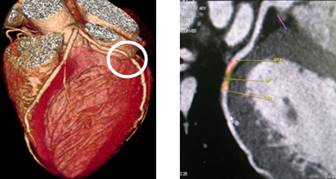

320排螺旋CT具备16cm宽覆盖探测器,实现动态容积扫描,360度的各向同性采集能力及[email protected]%密度分辨率的量子探测器,一次心跳全心脏采集,一圈扫描器官成像,一次检查完成多重任务,实现真正的动态容积体灌注及心脏、神经一站式检查;西门子Flash炫速CT扫描系统,具备两套同时旋转的X射线球管及探测器,实现了43cm/s的极快CT扫描速度和75 ms的时间分辨率,完成全胸扫描仅需0.6秒,使得患者做心脏扫描时无须食用β-受体阻滞药,亦无须屏气,并可实现低于1mSv的超低辐射剂量,配置第二代双能量、宽151级纯化能谱,组织鉴别能力进一步提高,可开展多达10余种双能量成像应用。

头颅一站式检查:320排容积CT覆盖范围达16cm,球管旋转一周可以覆盖整个脑组织,获得全脑0.5mm层厚各向同性全脑信息。一次扫描可以获得平扫容积图像、以时间为序列全脑动态3D-CTA图像(包括纯动、静脉期成像)及全脑灌注图像。一次检查即可排除脑出血、动脉瘤、动脉狭窄、梗塞、脑实质供血异常等多种病变及进行脑卒中筛查。

脑血管畸形CTA ,大血管成像:动态容积成像实现大范围动态血管检查